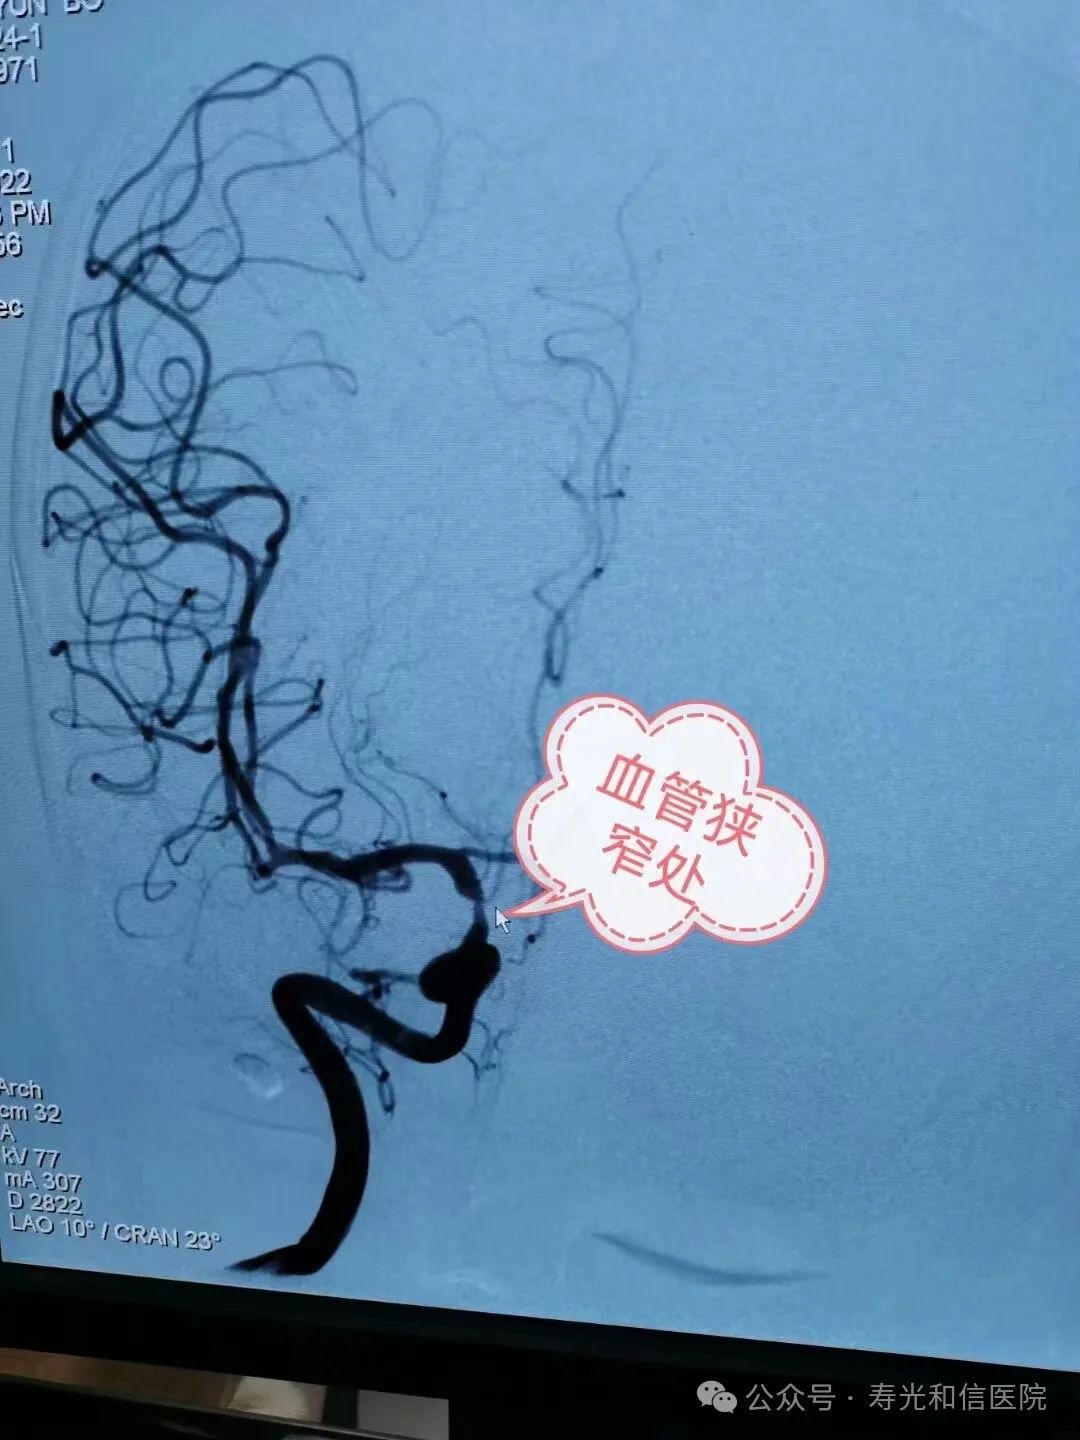

脑血管造影被公认为血管性疾病诊断的“金标准”,可以显示颈动脉、椎动脉、颅内血管本身的完整形态及改变,是检查和诊断脑血管有没有发生病变的重要手段,并且可以查看脑血管的脑血流情况、血管有没有变异、有没有狭窄等。

寿光和信医院神经科目前已独立完成150余台脑血管造影术,已具备常规开展脑血管造影术的能力。针对突发脑出血、原因不明、疑有动脉瘤或脑血管畸形的患者;反复头晕头痛、怀疑有大脑动脉狭窄或闭塞的患者;存在糖尿病、高血压、高血脂等脑动脉硬化高危因素的患者;突发一侧肢体无力、口角歪斜且在短时间内恢复及24小时内未恢复的患者进行脑血管造影检查,同时给予了精准的诊断及治疗,获得患者的一致好评。